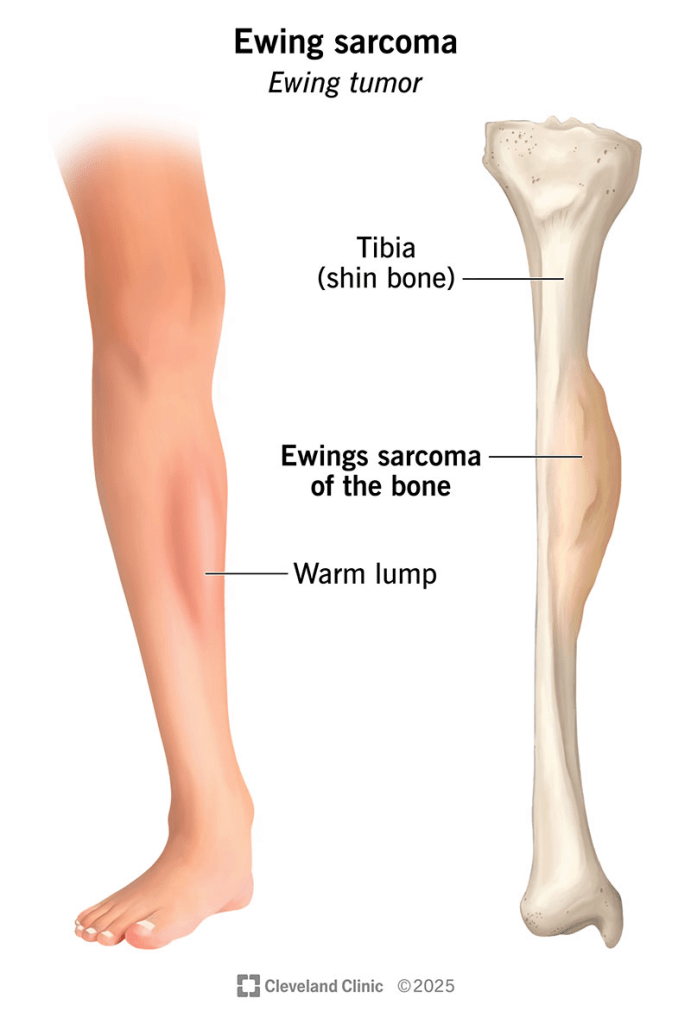

The Ewing family of tumors presents with symptoms that are largely dependent on the tumor’s location. Common indicators include intermittent pain that becomes constant over time, localized swelling, tenderness, and the presence of a palpable mass. Because these tumors can weaken the skeletal structure, affected individuals may experience fractures, while those with spinal involvement might suffer from weakness, numbness, or even paralysis. Systemic symptoms such as fever, fatigue, weight loss, anemia, and an increased white blood cell count can also manifest as the body reacts to the malignancy.

While these tumors can emerge in any bone or soft tissue, they most frequently target the pelvis, the long bones of the legs, particularly the femur, and the flat bones of the chest wall and spine. When the disease arises in the soft tissues, it is typically found in the trunk. Due to its aggressive nature, Ewing sarcoma frequently metastasizes to the lungs and other bones. Such spread can lead to severe secondary complications, such as breathing difficulties or pleural effusion if the respiratory system is compromised.